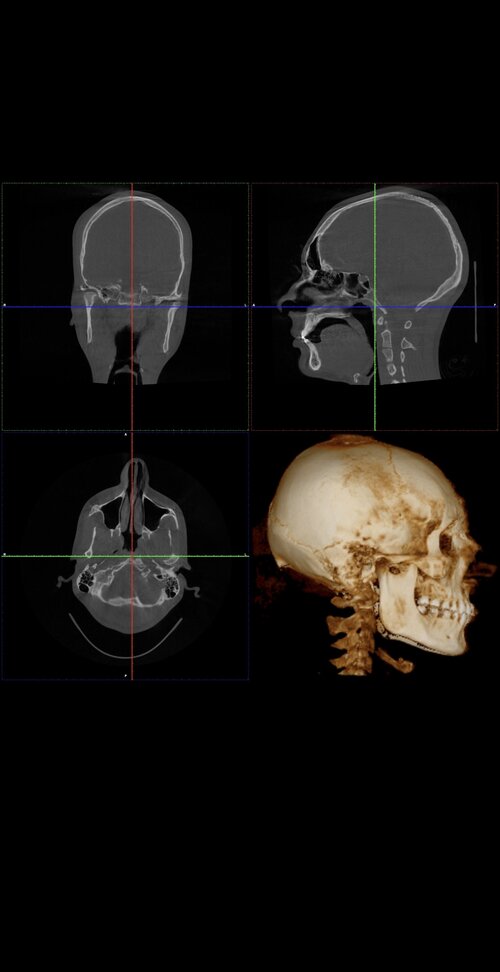

Ct scan for reference

Your mandible is recessed and your airway oropharynx cross section looks very small. Just imagine when you relax and lay down, your tongue goes back and blocks your airway even more.

The philtrum seems quite tall in the ct which may explain why your teeth show less. You have room for advancement in both jaws

Yes. Your lower front teeth are inclined forward